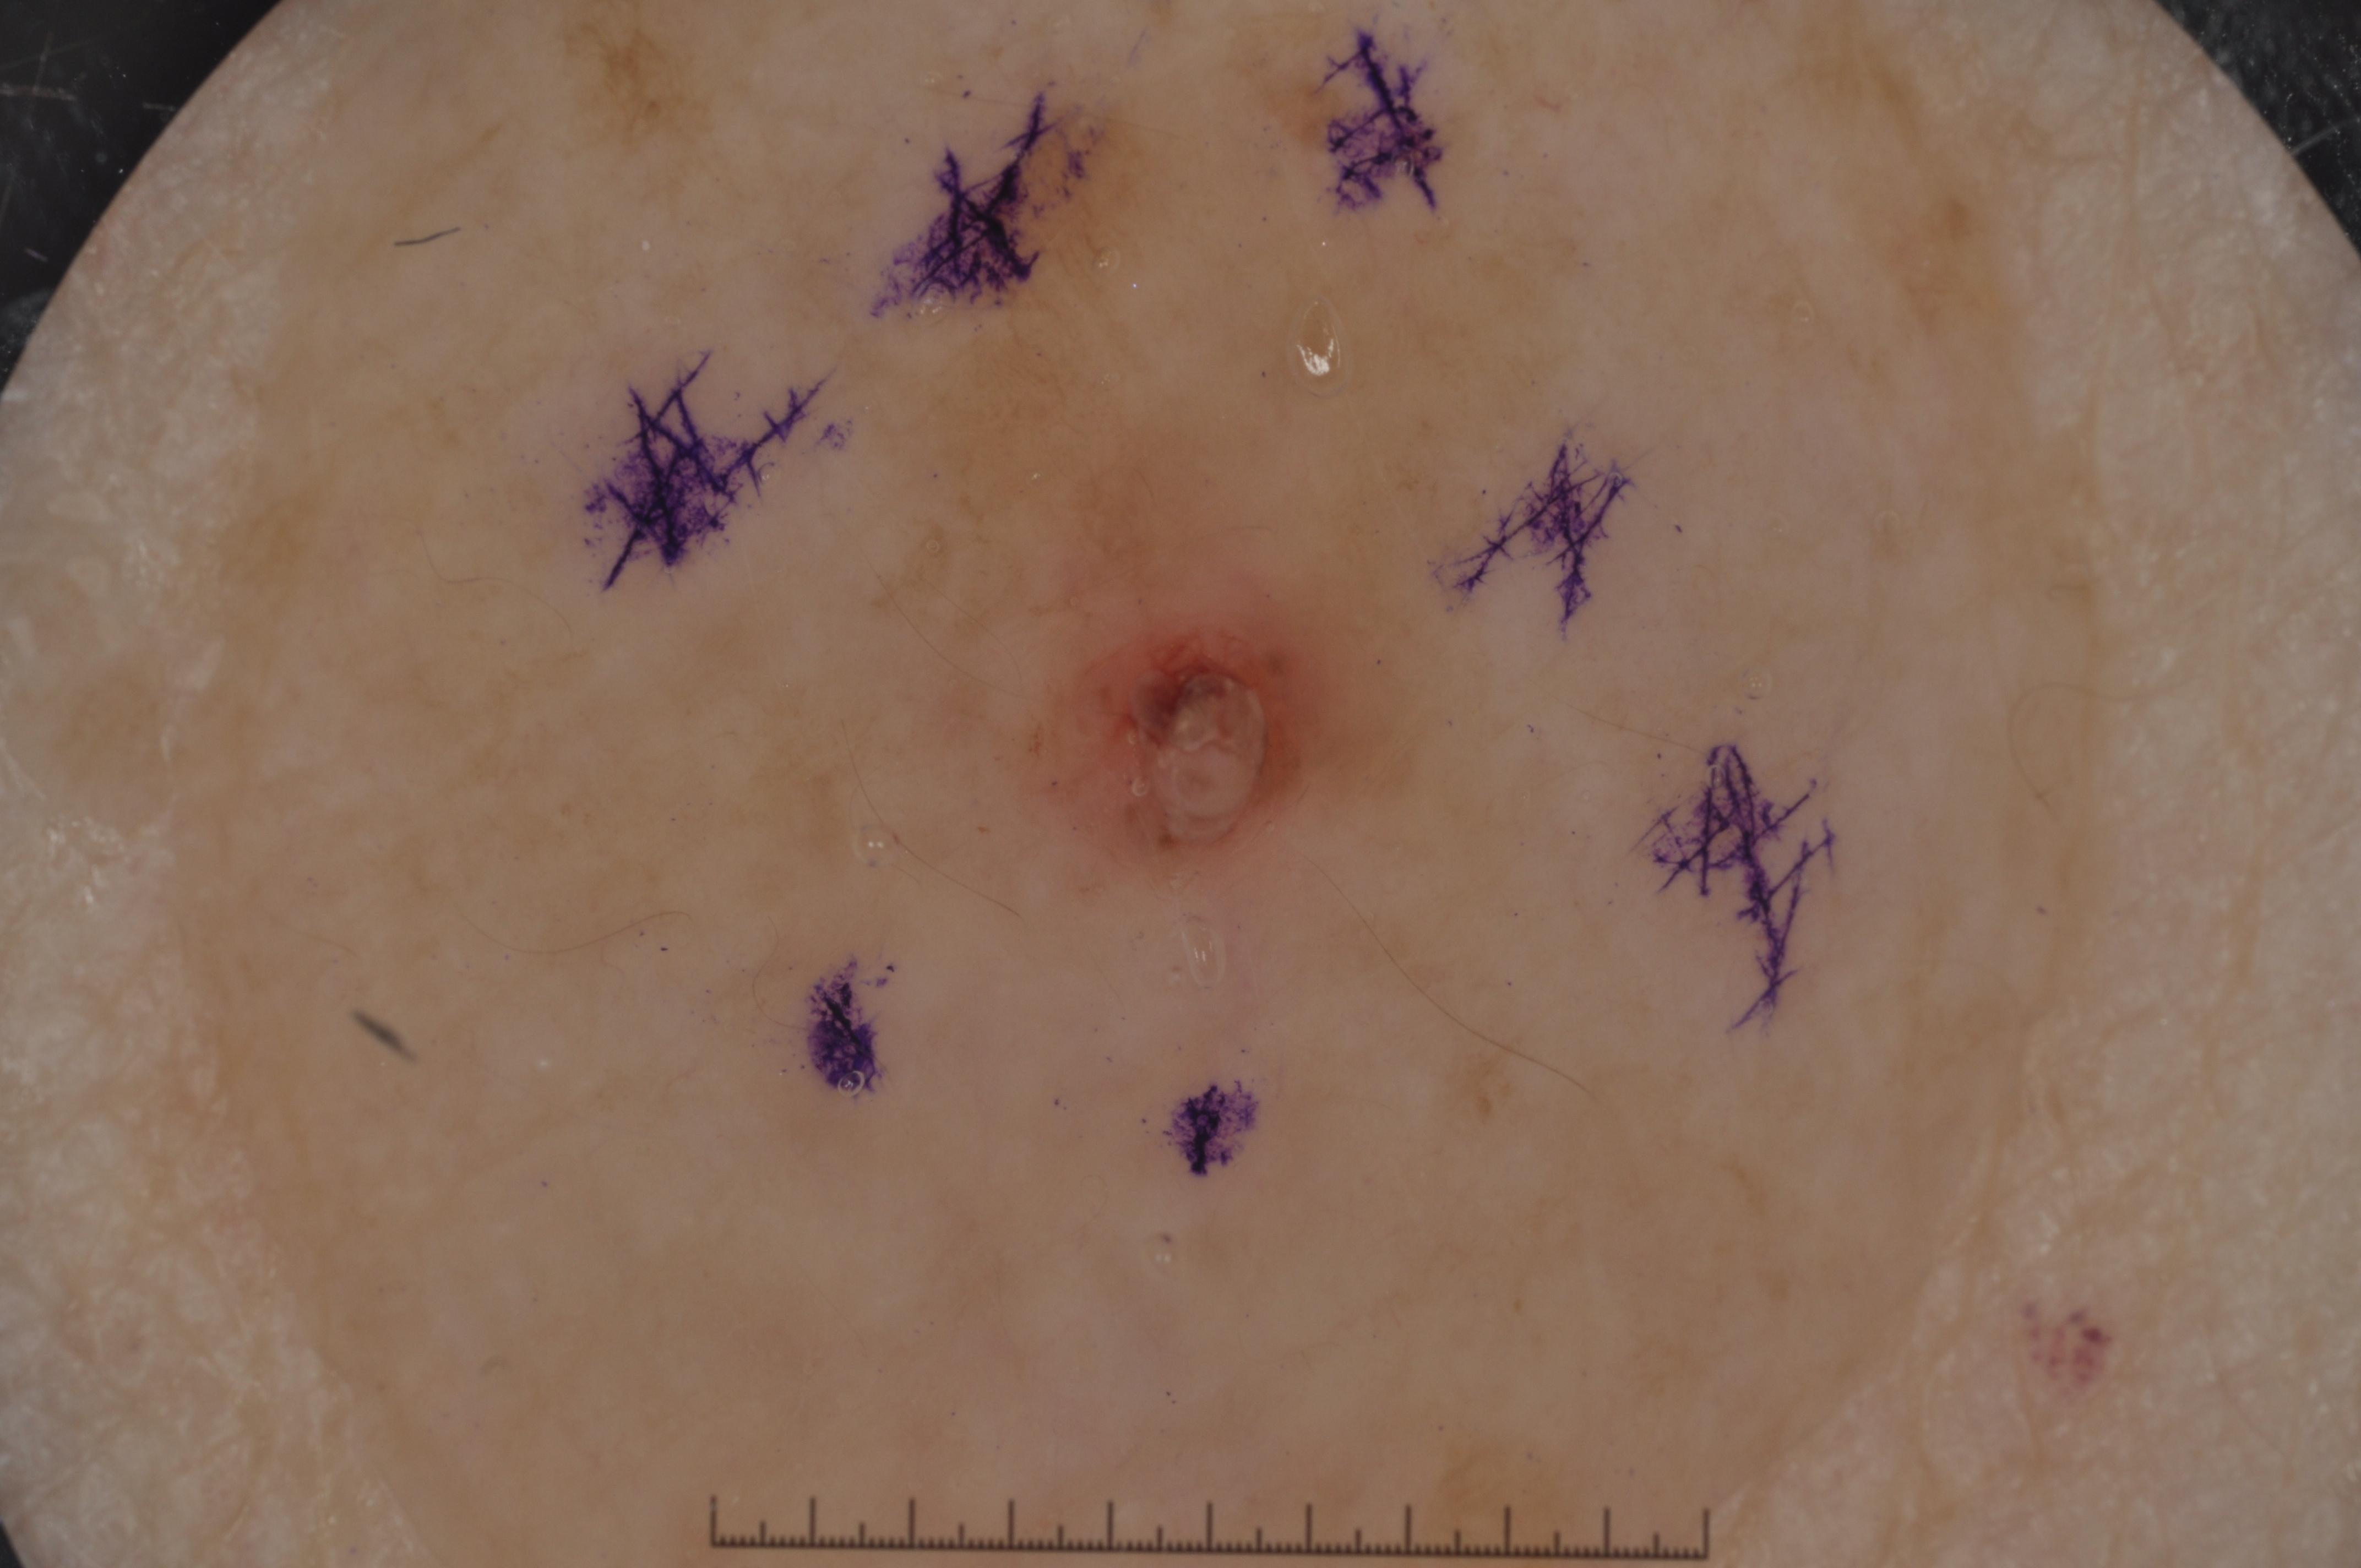

{

"age_approx": 75,

"anatom_site_general": "head/neck",

"concomitant_biopsy": true,

"dermoscopic_type": "contact non-polarized",

"diagnosis_1": "Malignant",

"diagnosis_2": "Malignant melanocytic proliferations (Melanoma)",

"diagnosis_3": "Melanoma in situ",

"diagnosis_confirm_type": "histopathology",

"image_type": "dermoscopic",

"lesion_id": "IL_7473586",

"melanocytic": true,

"sex": "female"

}